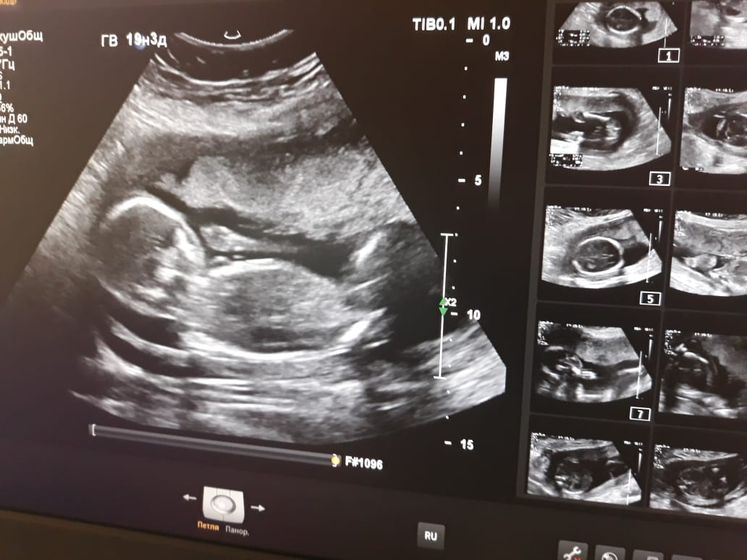

Сходили с мужем на второй скрининг, пустили его тоже в кабинет, но быстренько показали детку и выгнали в коридор ждать))) Слава Богу, все в порядке! Подтвердили нам девочку, ну я, собственно, и не удивлена=) С Тимкой чувствовала, что мальчик, и сейчас с Авелинкой чувствую, что девочка, с первых дней беременности)Не знаю, как так вообще, как говорится, невероятно, но факт=) Пост в основном для себя на память)

Спасибо!=)Ой, как я вас понимаю))))Я тоже дождаться не могла! Все усугублялось тем, что до 19ой недели я чувствовала шевеления, а в 19 резко перестала! Перестала после истерики своей и перепугалась жутко, думала, не дай Бог с ней что-то случилось… На УЗИ успокоилась=) А сразу после УЗИ начала опять ее чувствовать=)Насчет девочки-дай Бог вам ее, если так хочется=)))А вообще конечно пол совсем не важен, главное, чтобы здоровенький был=)